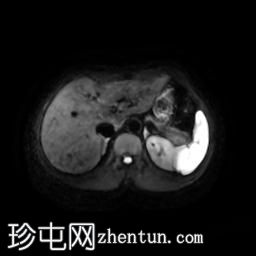

轴位

T1加权像

11.jpg

脂肪抑制像

此外,肝脏第二段左叶可见一 10 x 12 mm 的肝脏肿块,在重 T2 加权像上呈高信号。该病灶呈周边结节状强化,提示为血管瘤。肝脏第八段右叶可见一类似病灶,大小约 10 mm。

此外,右肾中极可见一大小约 5 mm 的肾皮质囊肿。